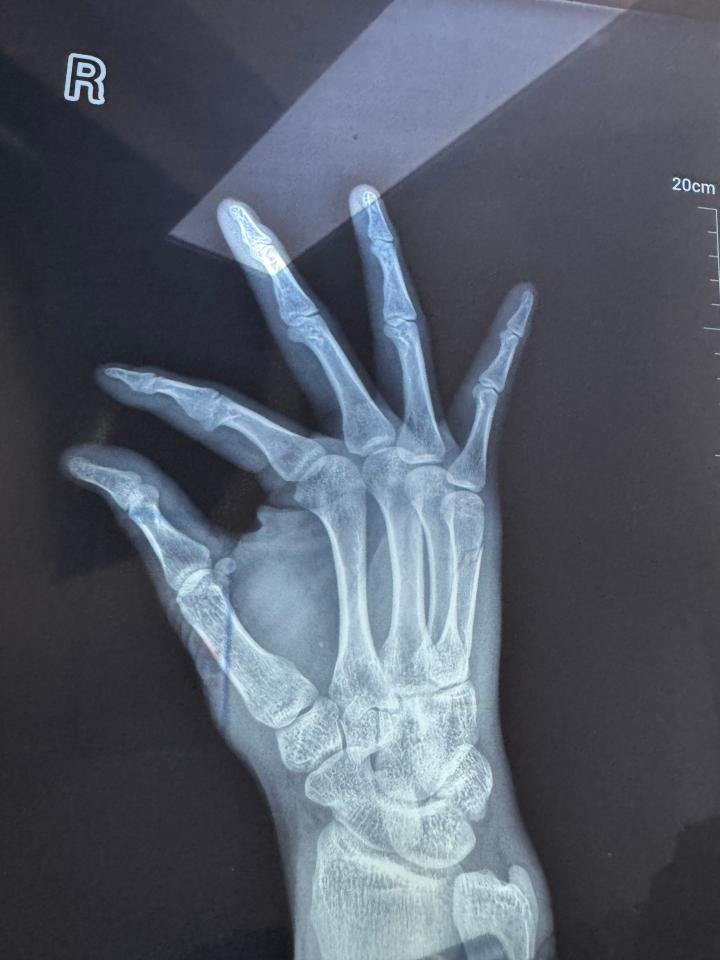

3月7日,CBA球队四川男篮官方发布消息,球员李玮颢在一次防守对抗后右手感到不适,经诊断为右手第五掌骨骨折,预计伤停12周。

我俱乐部球员李玮颢在2024-2025赛季CBA常规赛第三十六轮,3月5日四川丰谷酒业对阵吉林九台农商银行的比赛中,在一次防守对抗后右手感到不适,赛后前往医院就医;经专家诊断为右手第五掌骨骨折,预计伤停12周。